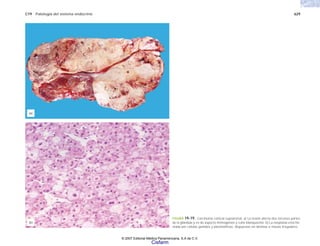

fibrinoide de la pared, engrosamiento endotelial e infiltrado inflamatorio mononu-